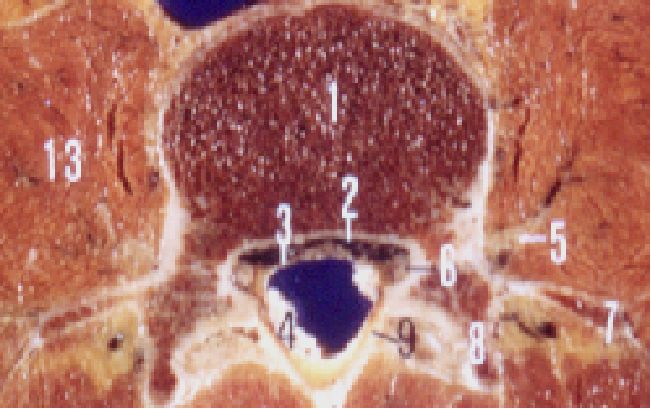

一、椎管的应用解剖

前壁:椎体、纤维环、后纵韧带。

后壁:椎弓和黄韧带。

两侧:椎弓根、上下关节突及关节囊,并以椎间孔向外开放。

黄韧带:起于上位椎管的下前缘,止于下位椎管的上后缘。

中央椎管:各腰椎椎孔形状,腰1、2多呈卵圆形,腰3、4多呈三角形,腰5多呈三叶形,其他尚可呈钟形、或橄榄形。因退变或其他病变、椎孔形状还可有不同改变。腰椎椎管自腰1、2间隙以下包含马尾神根.其被硬脊膜包围的部分形成硬膜囊,各种经根自硬膜囊发出后在椎管内的一段称为神经根管,以后分别自相应椎间孔穿出。

腰神经通道:腰神经根自硬脊膜囊发出后,经过较窄的骨纤维性管道,由椎间管穿出的径路统称为腰神经通道。此通道分为两段,第一段为神经根管,从硬膜囊穿出点至椎间管内口,第2段为椎间管

盘黄间隙:即椎间盘与黄韧带之间的间隙。

侧隐窝:侧隐窝位于侧椎管,也是神经根管的狭窄部分。